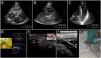

The vessels should be evaluated along both short and long axes. The target vessel should be selected based on patency (e.g., absence of thrombus, complete compressibility and phasic flow in veins; pulsatility, absence of plaques/stenosis and pulsatile flow in arteries), best depth (measuring the distance from the anterior wall of the vessel to the skin, in short axis) and size (measuring the anteroposterior vessel diameter) (Fig. 1A), course (straight better than tortuous) and the safest needle path assessing the relationship of the target vessel with pivotal structures such as the vein, artery or the pleura.42 As a rule of thumb, when selecting the catheter size, the anteroposterior diameter of the vessel corresponds to the maximal catheter size (e.g., 5 mm corresponds to a catheter up to 5F). In addition, at least 50% of the catheter length should lie in the vessel; therefore, longer catheters are needed for deeper vessels, and vice versa.

Ultrasound-guided vascular cannulation. A) Preprocedural assessment of a peripheral vein for ultrasound-guided cannulation. The anteroposterior diameter of the vein (continuous yellow line, Distancia 2) and distance from the vein to the skin (continuous green line, Distancia 1) are measured. B) In-plane cannulation of the internal jugular vein (v); arrows, needle shaft; arrowhead, needle tip. C) Out-of-plane cannulation of the internal jugular vein (v); a, common carotid artery; arrow, needle. D) The guidewire is observed in the vein lumen (arrows) before placement of a long catheter in the basilic vein (e.g., midline catheter); v, vein. E) A peripheral venous catheter (arrow) is observed in the lumen of a deep vein of the arm (short axis); v, brachial veins; a, brachial artery. F) A peripheral catheter (arrows) is depicted in the lumen of a superficial vein in the long axis; v, vein. G) Subperiostial flow is observed on color Doppler after intraosseous needle insertion. H) Pseudoaneurysm as a complication of femoral arterial catheterization; black arrows, pseudoaneurysm cavity; white arrows, pseudoaneurysm neck; a, common femoral artery; v, common femoral vein.

After disinfecting the skin and applying a local anesthetic under real-time ultrasound guidance, the needle is inserted in-plane or out-of-plane (Fig. 1B and C), and the catheter is accommodated using the trocar or Seldinger technique. When using the latter, the guidewire should be confirmed in the vessel before progressing the dilator (Fig. 1D).

To assess the CVC tip position, one operator injects agitated saline or normal saline through the distal port of the CVC, while a second operator performs simultaneously a subcostal 4 chamber view or an apical 4 chamber view. The immediate (within 2 s) appearance of turbulent flow in the right atrium is known as the rapid atrial swirl sign (RASS) and predicts with excellent sensitivity and specificity for a correct catheter tip positioning45 (Video 1).

The intravenous position of a peripheral catheter is assessed by direct visualization in the short and/or long axis (Fig. 1E and F) and the flush test (Video 2).

Intraosseous cannulation is not performed under real-time ultrasound guidance; however, its correct position may be evaluated using color Doppler when subperiosteal flow is observed after flushing the line (Fig. 1G).47

PosprocedurePOCUS is performed to assess complications, such as hematoma, pneumothorax (rechecking the lung sliding), infiltration, and catheter-related thrombosis. The distal flow should also be assessed after arterial cannulations, while a pseudoaneurysm should be ruled out (Fig. 1H), when the catheter is removed.